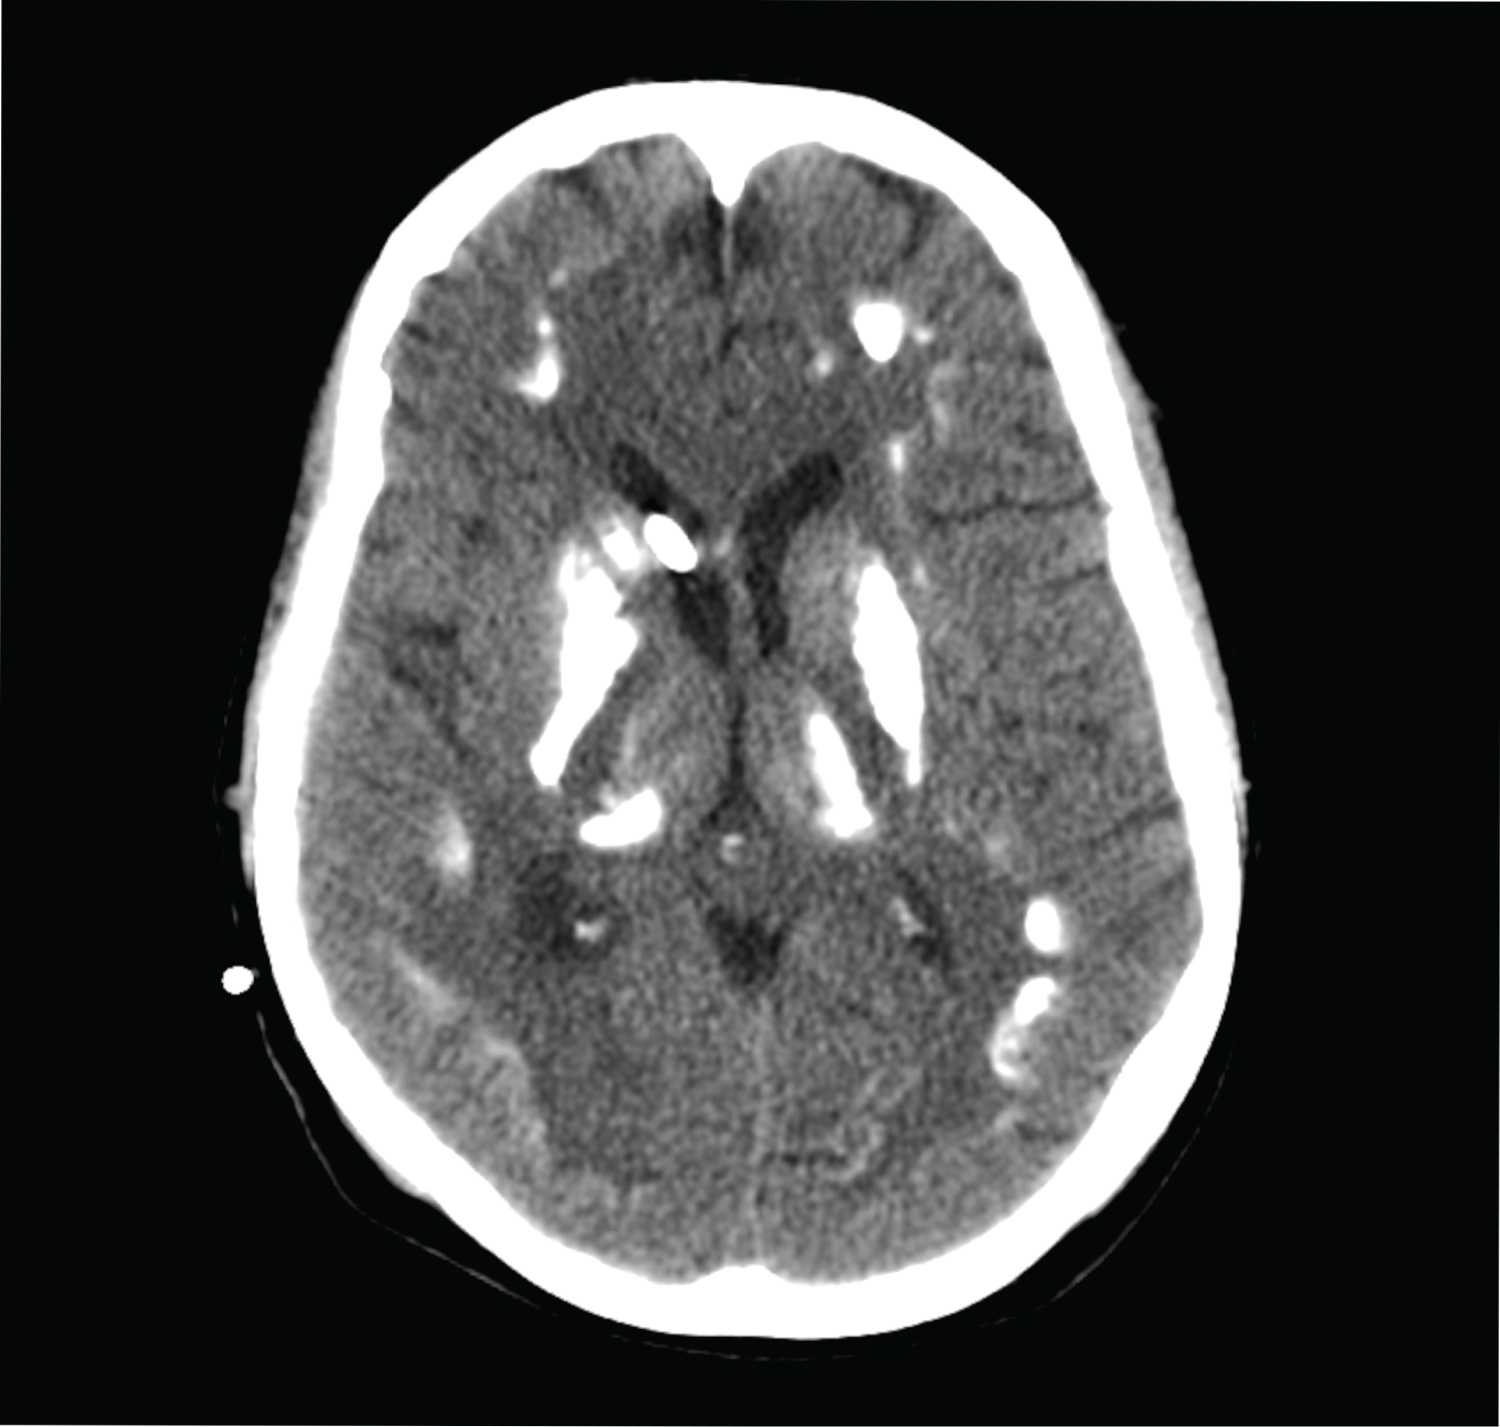

27-year-old female patient who was brought to the Emergency Department of our hospital with the complaints of severe headache and vomiting. Her general condition was moderate, she was conscious, disorientated, and cooperative. Pupils were isochoric, bilateral light reflex was positive, and there was no lateralized motor deficit. Glasgow Coma Score was evaluated as 14 points. Blood pressure was measured to be 130/80 mmHg, pulse was 90/min, respiratory rate was 14/min, and fever measured 36 centigrade degrees. Head CT reported as hyperdense appearance compatible with intraventricular hematoma in both lateral ventricles and at the level of 3rd and 4th ventricle (Figure 1). Disseminated subarachnoid hemorrhage and additionally widespread calcification across bilateral basal ganglia, thalamus, and subcorticalwhite matter detected. Patient first taken to the OR to place an external ventricular drainage (EVD) catheter (Figure 2). Then DSA performed which revealed saccular aneurysmatic filling with 5*3 millimeters in diameter at the apex of the right Internal Carotid Artery just before theM1 segment of Middle Cerebral Artery. Endovascular coil placement was performed for aneurysm treatment (Figure 3). Then patient was taken to the neurosurgery intensive care unit for post-operative (PO) close follow-up. On the PO-5th day, she was taken to the in-patient floor due to wellness in her general condition. Control angiography showed successful closure of the aneurysm (Figure 4). Patient followed up three days with EVD closed as the clarification of the color of the cerebrospinal fluid in the catheter and resorption of the intraventricular hemorrhage in the control tomography observed (Figure 5). As no changes seen in the clinical status EVD catheter removed and patient discharged to home on the PO-12th day.

Figure 2: Control brain tomography after external ventricular drainage for drainage of existing bleeding. View Figure 2